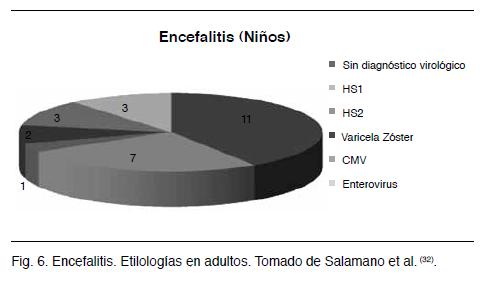

En este trabajo se detectaron 44 pacientes con clínica y paraclínica sugestivas de encefalitis viral; 21 de estos casos no tuvieron diagnóstico etiológico viral por PCR; 27 casos fueron encefalitis en niños mayores a seis meses y 17 en adultos; 17 tuvieron diagnóstico virológico vinculado a virus de la familia herpes: 11 por HSV 1, 3 por CMV, 2 por VZ y 1 por HSV 2. Es de destacar que los hallazgos de CMV, VZ y HSV 2 fueron en niños. Ninguno de los pacientes tenía circunstancias de inmunodepresión (Figuras 6 y 7).